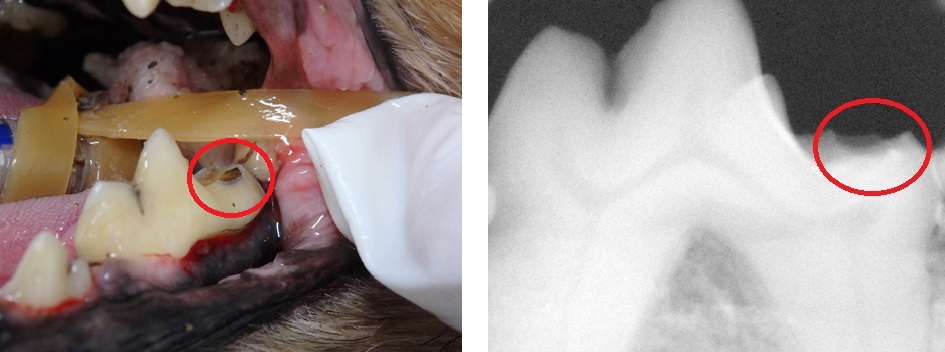

.jpg)

↑虫歯を疑う病変

ただし犬では虫歯ではない

歯の吸収病変の方が

遭遇することが多いです。

この場合、腫瘍の可能性も

考慮する必要があります。

↑犬の歯で認められた吸収病変